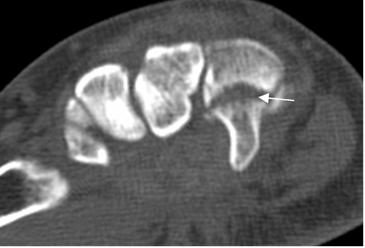

Fig 44 B. Fractura del ganchoso.

TAC axial: Fractura transversa en la apófisis del ganchoso.